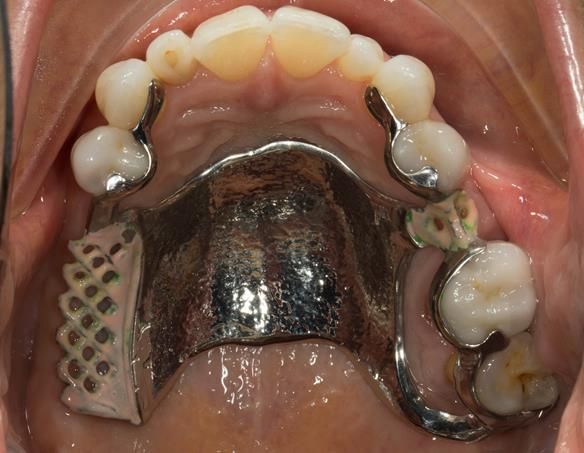

This newsletter describes in step by step detail Angela's transition through immediate partial dentures to crown supported definitive metal based dentures.

The clinical situation and treatment process is shown in detail below with photographs. I (Finlay Sutton) provided the clinical work and Rowan Garstang provided the technical work.